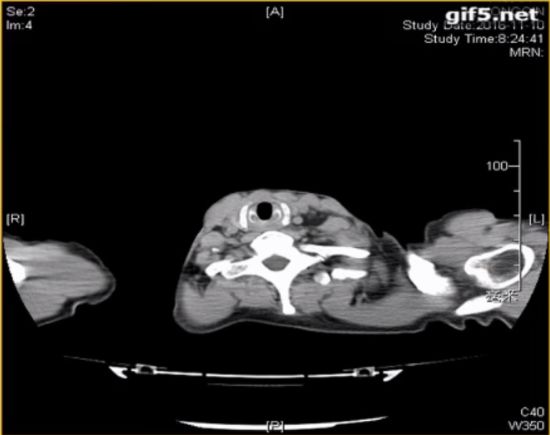

◆颈部CT

咽部及主支气管颈段异物,双侧颈部软组织间隙及胸壁皮下积气,气管破裂可能

◆胸部CT

-主气管颈段及右肺下叶支气管异物,双侧胸壁、颈部皮下及纵隔内积气,右肺少许炎症